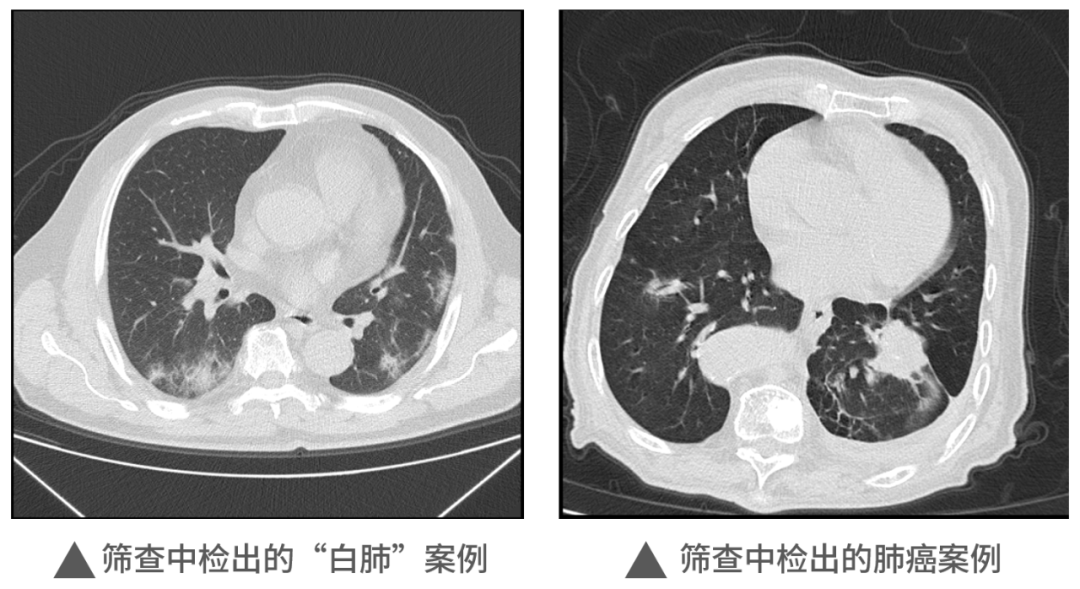

本次活動中,明峰醫療移動CT充分展現了它的適應性和便利性,在近1000人的檢查中,共查出肺部炎癥300余例,肺部結節560例,同時檢出一例肺癌病例。這對于本次篩查人員今后胸部健康和治療提供了重要的參考和指導,為全區居民和企業提供了堅實的保障,同時大大提升區內的醫療健康保障能力。未來,明峰醫療醫療仍將持續致力于高端醫療設備的普惠應用。作為杭州市錢塘區的區內企業,將沿著區委區政府“四個全域”建設的發展規劃和區衛健系統提出的目標及要求,發揮人才企業的優勢,以科技創新引領企業發展,為區內產城融合的服務配套做好應有的保障和支撐工作,探索政產學研合作的新思路新模式,共建共享,共同成長,造福更多的人民百姓,在書寫中國式現代化的錢塘答卷上也添上濃墨重彩的一筆。